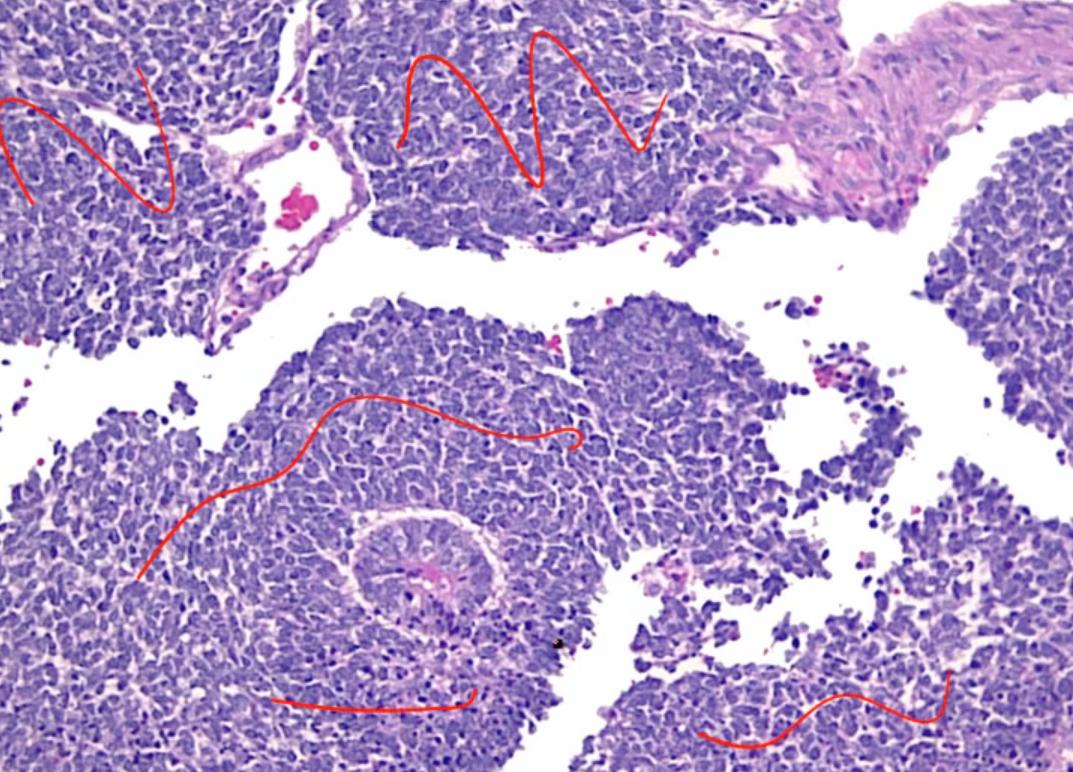

Transitional Cell Carcinoma

flat pathway: high grade flat tumor then invades. Early p53 mutation

papillary: low grade papillary tumor that progress to high grade and then invade. Not association with p53